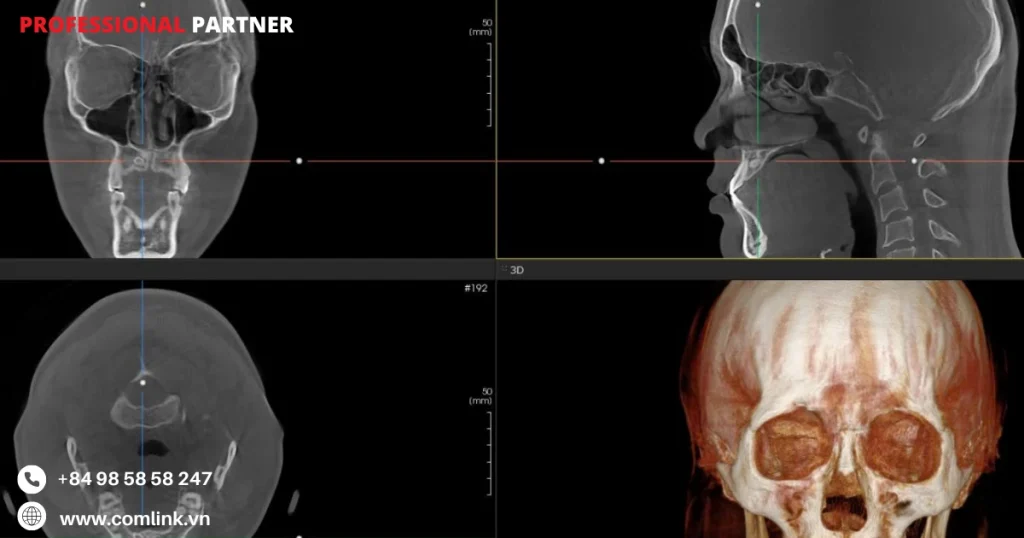

Máy chụp cắt lớp điện toán Cone Beam (CBCT) là một công nghệ hình ảnh phức tạp đóng vai trò then chốt trong nha khoa hiện đại.

Không giống như máy X-quang truyền thống, máy CBCT cung cấp hình ảnh ba chiều chi tiết về răng, xương hàm và các cấu trúc xung quanh với độ rõ nét và độ chính xác đặc biệt.

Bằng cách sử dụng tia X hình nón xoay quanh đầu bệnh nhân, máy CBCT thu thập dữ liệu thể tích có thể được tái tạo thành hình ảnh 3D có độ phân giải cao.

Hình ảnh chất lượng cao

- Máy CBCT cung cấp chất lượng hình ảnh vượt trội so với chụp X-quang nha khoa thông thường.

- Do đó cho phép hiển thị chi tiết các cấu trúc giải phẫu và các bất thường.

Chẩn đoán chính xác

- Hình ảnh 3D do máy CBCT tạo ra hỗ trợ các chuyên gia nha khoa chẩn đoán chính xác tình trạng răng miệng.

- Từ đó lập kế hoạch điều trị và đánh giá tính phù hợp của các thủ thuật như cấy ghép nha khoa hoặc can thiệp chỉnh nha.